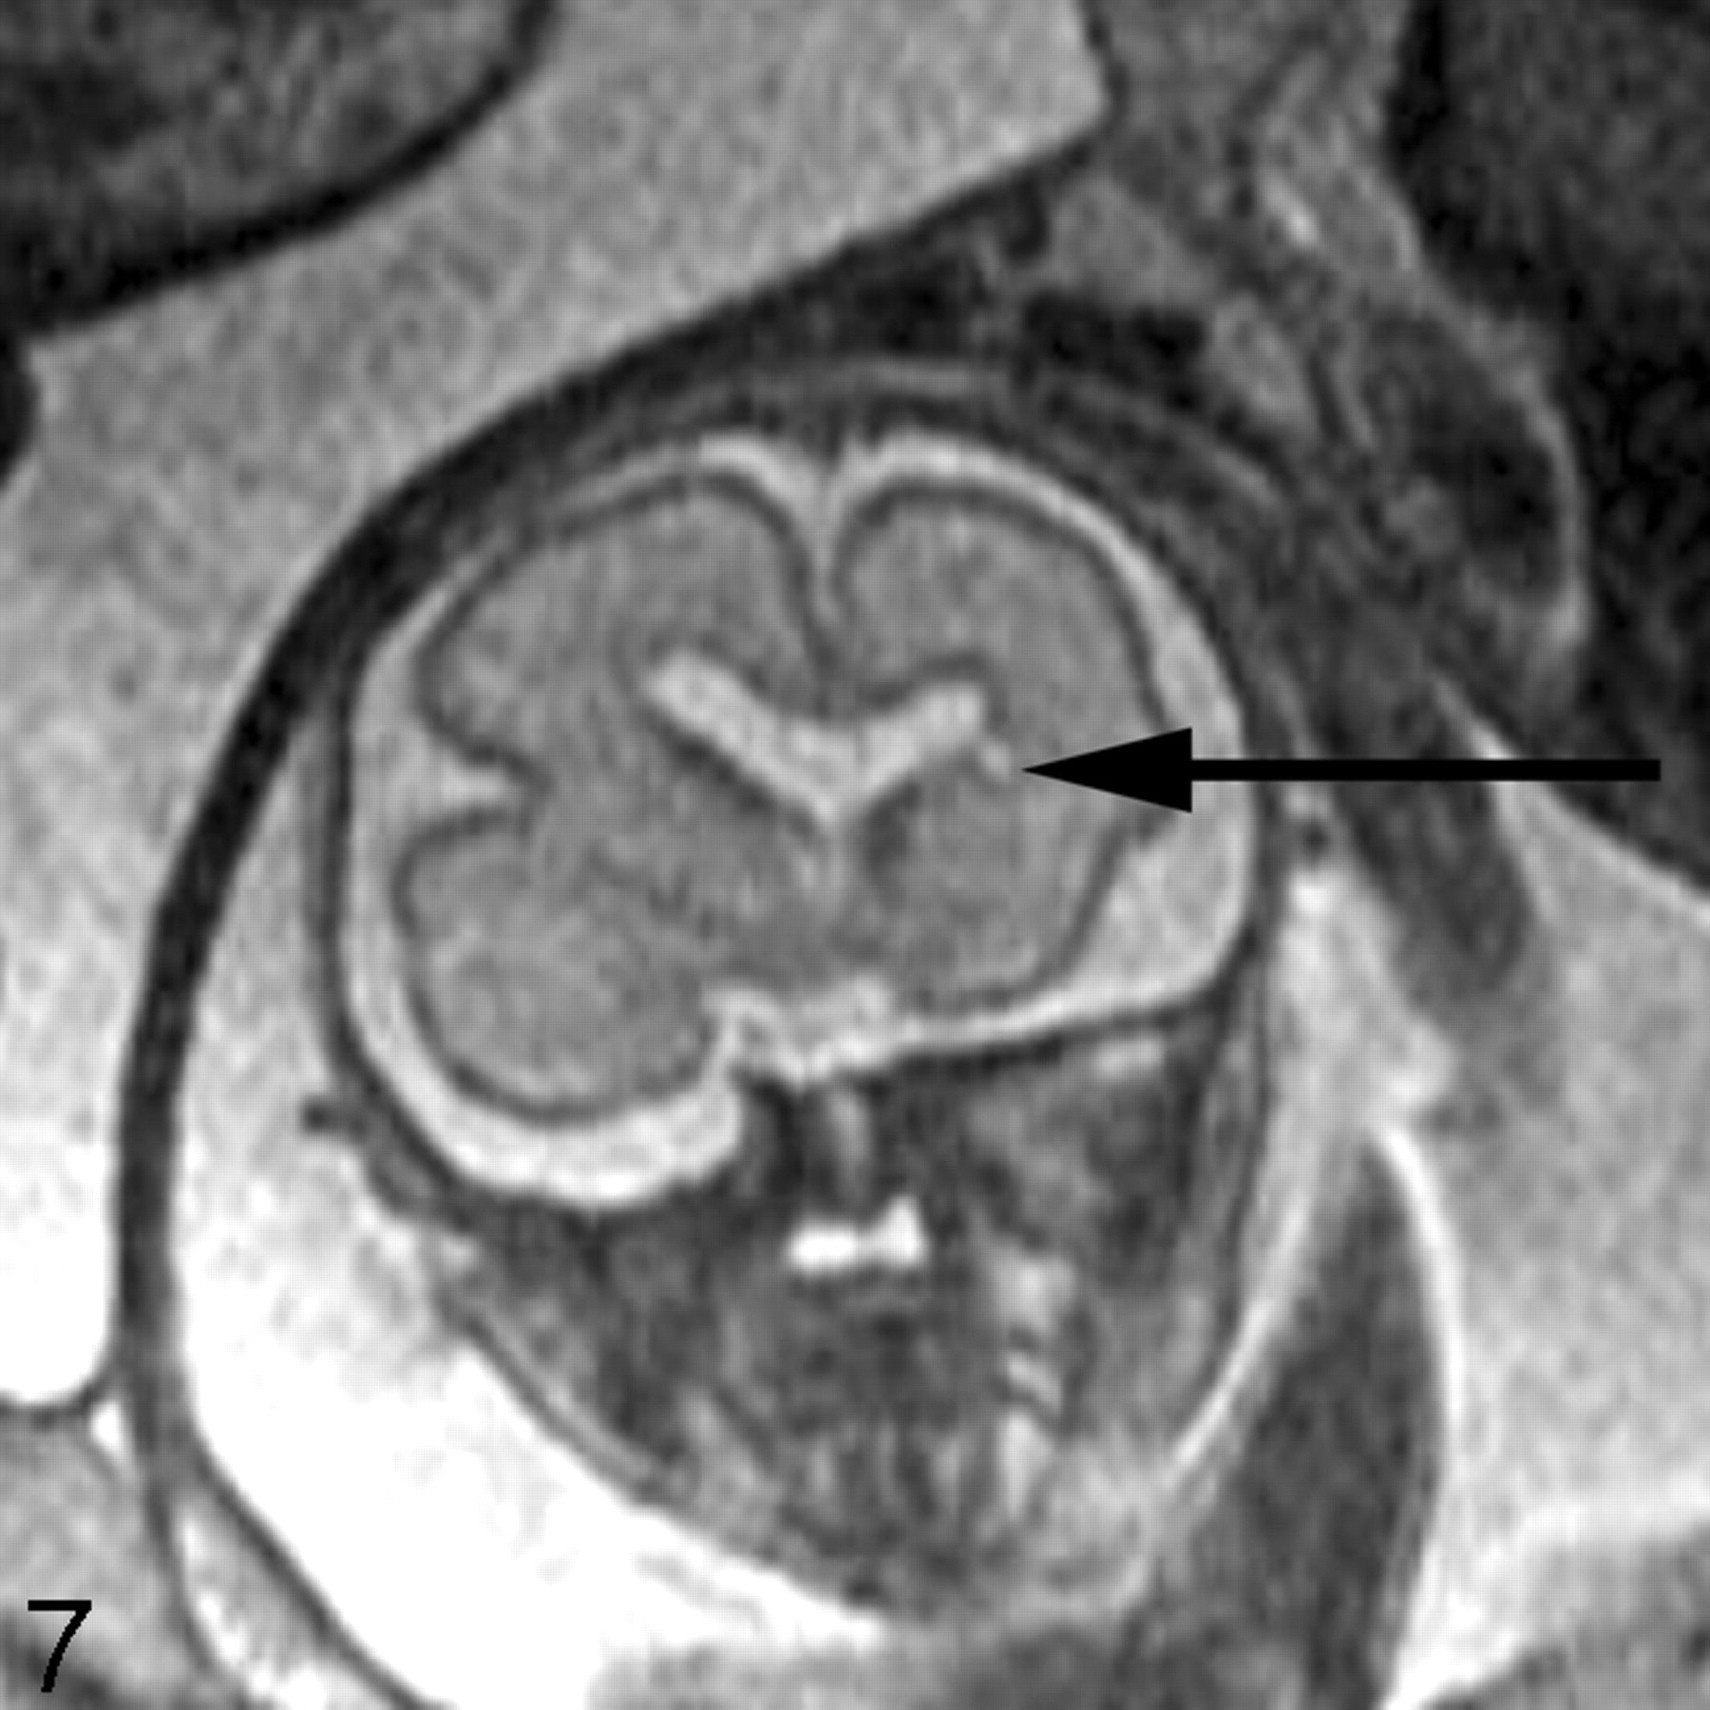

The intervening parenchyma appears relatively bright on the T2-weighted images, and dark on the T1-weighted images, especially before approximately gestational week 20. Girard and Raybaud initially described a multilayered pattern on T1-weighted images beginning at approximately 20 weeks and persisting until approximately 28 weeks.7,45 It is characterized by 3 bands of alternating T1 signal intensity between the germinal matrix and developing cortex. An excellent study by Kostovic et al42 demonstrated that the different layers visible on the fetal MR images represent the different developing layers of the fetal brain. In particular, the first layer superficial to the germinal matrix represents the periventricular zone (dark on T1-weighted images); the next layer represents both the subventricular and intermediate zones (bright on T1-weighted images); and the next layer, which is just deep to the developing cortex, represents the subplate (dark on T1-weighted images). A similar multilayered pattern is seen on T2-weighted images in the normally developing fetus (Fig 2).46,47

Coronal SS-FSE T2-weighted image at gestational week 23 demonstrates a multilayered pattern. The deepest layer is low in signal intensity and represents the germinal matrix (arrowhead). Immediately superficial to the germinal matrix is a hyperintense layer that represents the periventricular zone (arrow). Immediately superficial to the periventricular zone is a hypointense layer that represents the subventricular and intermediate zones (double arrows). Superficial to this hypointense layer is a band of high signal intensity that represents the subplate (double arrowheads). The most superficial layer of the developing brain represents the developing cortex and marginal zone and is isointense to the germinal matrix (triple arrows).